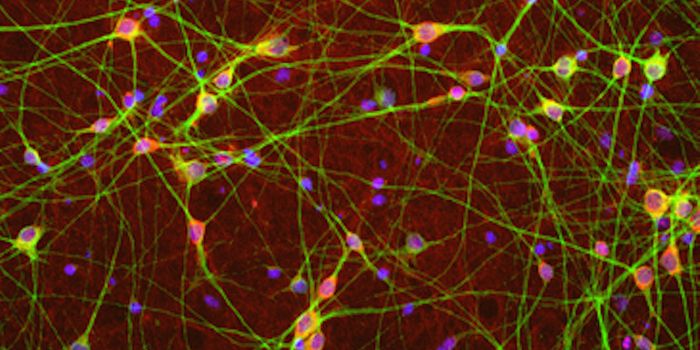

FEB 01, 2016NeuroscienceNeurons are incredibly tiny, but they have a big task in the brain. Cells within the nervous system, called neurons, are ...

SEP 22, 2015NeuroscienceStem cells can create tissue models that reflect human physiology. These stem cell-derived models can be used in researc ...

JUN 08, 2015NeuroscienceHow do we learn? Why do we get frustrated?